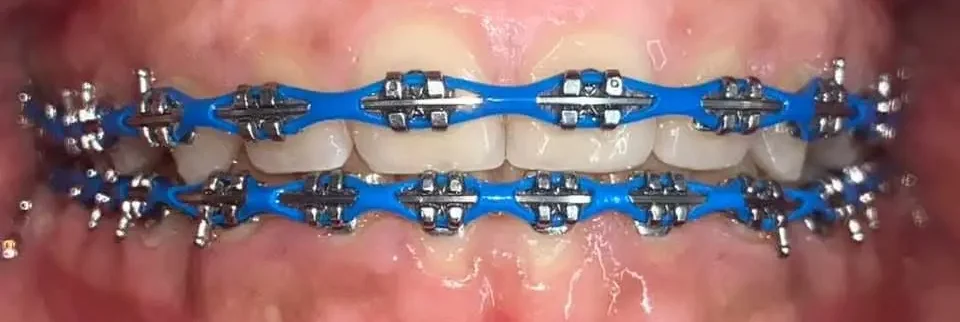

Corregimos la posición de los dientes y la mordida para lograr una sonrisa armónica y una función dental óptima. Este tratamiento, realizado por un especialista en Ortodoncia, transformara tu sonrisa y evitara problemas futuros en tu salud bucal.

Agenda tu citaOrtodoncia(Brackets)